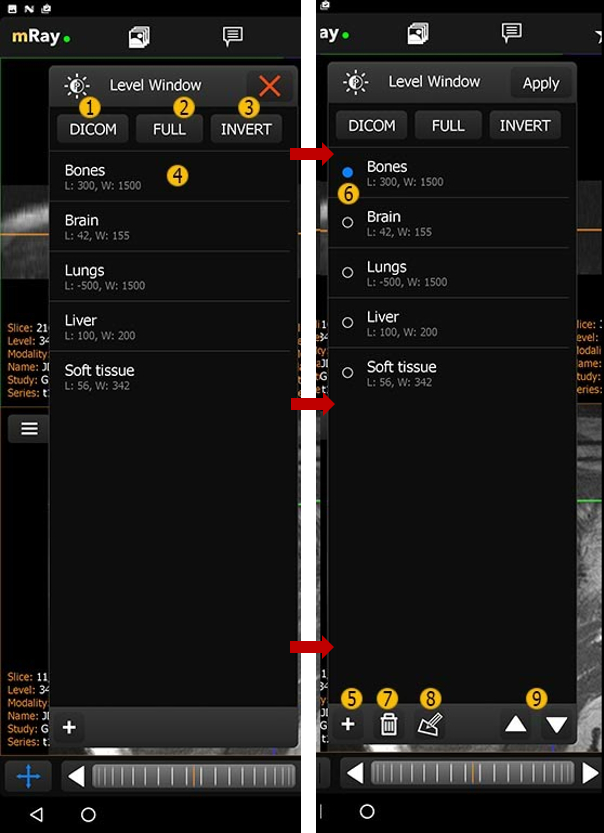

10.6. Level-Window-Voreinstellungen

mRay bietet die Möglichkeit vordefinierte Grauwertbereiche zu speichern. Diese können über das Level-Window-Voreinstellungsmenü ausgewählt werden. Bitte beachten: Wenn Sie diese Einstellungen ändern, werden Sie nur für das aktuelle Gerät gespeichert und nicht systemweit.

-

DICOM: Setzt das Level Window gemäß den Werten der DICOM Tags des Bildes.

-

FULL: Setzt Level Window auf das gesamtes Spektrum an Grauwerten.

-

INVERT: Setzt Level Window auf das gesamte Spektrum an Grauwerten, jedoch invertiert.

-

Level-Window-Voreinstellung

-

Einfacher Klick: Setzt diese Fensterungs-Einstellungen für die aktuelle Ansicht.

-

Doppelter Klick: Setzt diese Fensterungs-Einstellungen für die aktuelle Ansicht und schließt das Voreinstellungen-Fenster.

-

Gedrückt halten: Auswahl dieses Eintrags/Mehrfachauswahl.

-

-

Hinzufügen: Neue Voreinstellung hinzufügen.

-

Eine oder mehrere Einträge auswählen

-

Löschen: Löschen der selektierten Voreinstellung.

-

Bearbeiten: Selektierte Voreinstellung bearbeiten (Level-Window-Voreinstellungen bearbeiten).

-

Aufwärts/Abwärts bewegen eines Eintrags.